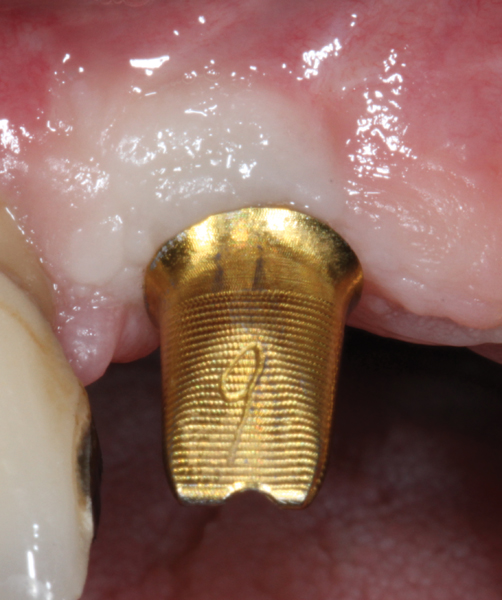

Fig 8. Some implant abutments flare drastically at the connection with the implant. This will compromise blood supply to the area, encroach on the peri-implant biologic width, and likely result in a more apical position of the bone and soft tissue. This design should be modified for use in the esthetic zone.

Figure 8

Fig 9. The flared area is recontoured to a diameter no bigger than that of the implant. This is done preoperatively with a heatless stone wheel and then polished.

Figure 9

The narrowed abutment emergence profile will minimize encroachment on the peri-implant

bone. This design will help to preserve the peri-implant tissue and may enhance the final outcome.